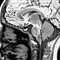

• 人类大脑存"悲惨分子" 蛋白质作祟或为压力来源人类大脑存"悲惨分子" 蛋白质作祟或为压力来源 蛋白质CRF1即为“悲惨分子”   近日科学家发现了大脑里的“悲惨分子”,它可能是导致所有压力和焦虑感受的根源。   英国一家医药公司的一支研究小组利用世界上最强大的X射线机器之一研究大脑的…